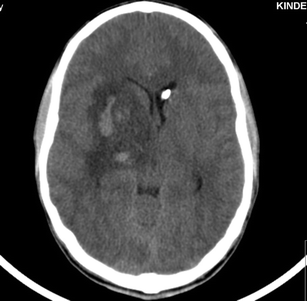

In the management of severe head injuries, the use of intraventricular catheters for intracranial pressure (ICP) monitoring and the option of cerebrospinal fluid drainage is gold standard. In children and adolescents, the insertion of a cannula in a compressed ventricle in case of elevated intracranial pressure is difficult; therefore, a pressure sensor is placed more often intraparenchymal as an alternative option.

In cases of persistent elevated ICP despite maximal brain pressure management, the use of an intraventricular monitoring device with the possibility of cerebrospinal fluid drainage is favourable. We present the method of intracranial catheter placement by means of an electromagnetic navigation technique.